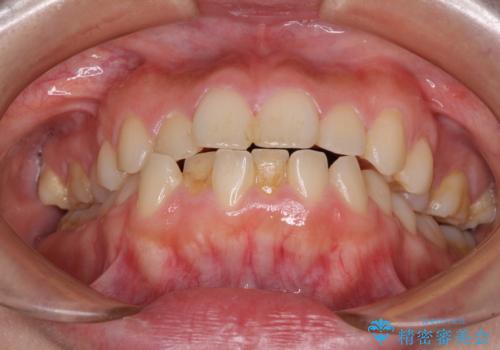

- 前歯が突出しているために口が閉じられないとのことで来院された患者様です。

上下ともに顎が小さく、歯列が前方に突き出していたため、上下左右の第一小臼歯4本を抜歯し、口元の突出感を改善していくこととしました。

口元の突出感が改善されると睡眠中の口呼吸が予防でき、鼻炎などの疾患予防に繋がると言われています。